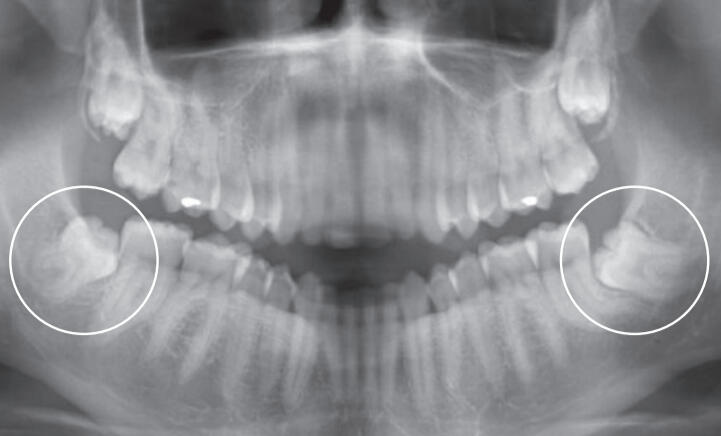

On parle de dent incluse lorsqu’elle reste entièrement dans l’os, et de dent semi-incluse lorsqu’elle est partiellement sortie. Ces situations favorisent parfois la stagnation alimentaire, l’inflammation locale et des épisodes douloureux.La décision thérapeutique dépend notamment :

de l’orientation de la dent (verticale, inclinée, horizontale)

de sa position anatomique

de l’état de la dent voisine